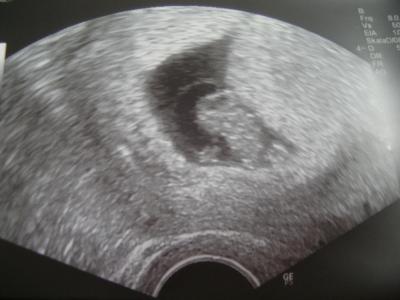

Hallo ihr Lieben, ich bin auch zurück und alles ist super, ich hab zwar noch ein bissel Blut beim Abstrich, aber das macht nix. Knirps ist jetzt 1,6 cm groß und man kann schon erkennen, daß es kein Badeentchen wird, sowie auf dem letzten US Bild Herzchen schlägt ganz dolle und meinen Mutterpass habe ich auch bekommen. Den nächsten Termin habe ich am 11.01. und am 15.01. Termin in der Klinik. LG

Bild zu Bin auch zurück mit Bild - Forum für August - Mamis

huhu Das sind doch super nachrichten :) Freue mich für dich und ein Schönes US Bildchen